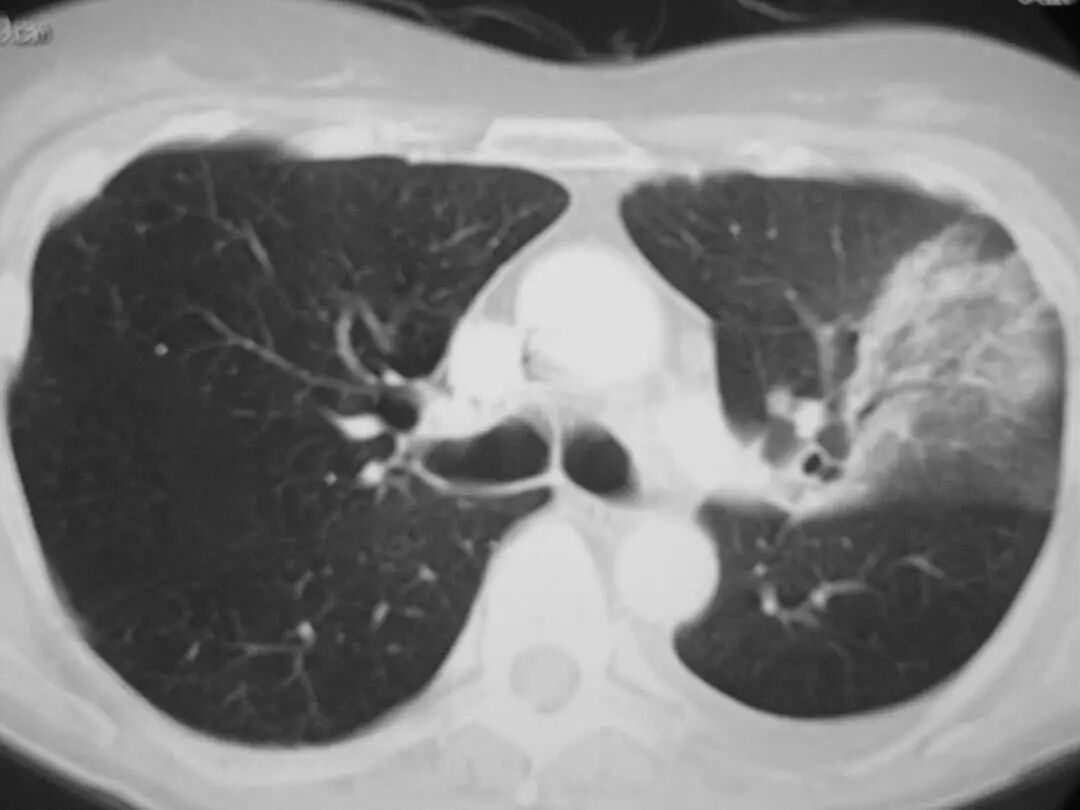

图1.7 CT扫描显示左下叶模糊的气腔浸润。